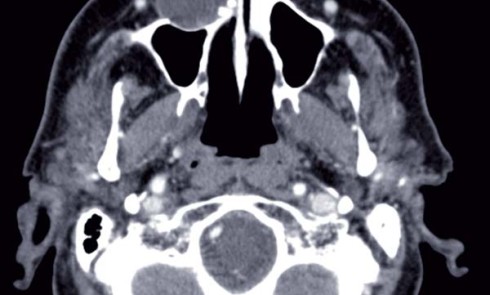

Article réservé à nos abonnés Diagnostic, traitement et reconstruction d’une ostéolyse importante du maxillaire édenté total

ObservationUn patient de 74 ans a été adressé dans le service de chirurgie maxillo-faciale du Centre Hospitalier Intercommunal de Villeneuve...